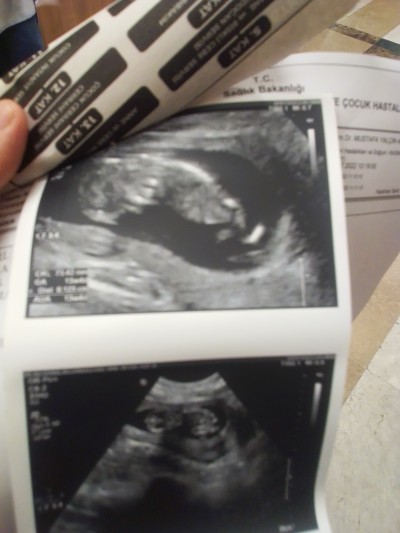

Kızlar tahmin yapabilen varmı

Kızlar sizce kız mı erkek mi

Resim çok bulanık haftası da küçük galiba ama kız gibi duruyor

Evet canım küçük daha 13 hafta sağol

Benimkide aynii bu pozisyonda duruyodu erkek dediler

Canim 14. Haftamda cinsiyeti icin gittik ayni boyle duruyodu doktor tahmin yapamadi ama 18. Haftamda detayli ultrasona girdim erkek dediler detaylinda kesin belli olur

Benim oğlumun pozisyonu aynı hayırlısı olsun:)

Erkek sanki benimkide bu şekilde duruyordu ama 13 haftada doktor kız demisti sonra 17 haftada yeniden bakınca erkek dedi doktor

Ayni benimki de böyleydi erkeekk